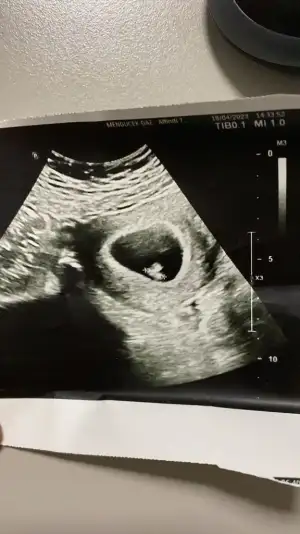

ben tüp bebek sürecindeyim. 30 mart tarihinde 5. gün embriyosu transfer edildi. geçtiğimiz cumartesi keseyi gördüm . 29 nisanda kalp atışı için gideceğim nasipse. aranıza 2. kez anne olmak için katılıyorum inşallah rabbim hepimizin sağlıkla kucağına almasını nasip eder.

Merhaba arkadaşlar. Dün doktor kontrolüne gittik. 7+4 teydik ama doktor 7+2 dedi. Çok şükür kalp atışını da duyduk. Bizim tam sınırda olacağı için hem Kasım hem de Aralık ayında paylaşıyorum :)

• IMG-20230418-WA0001.webp

IMG-20230418-WA0001.webp

39,1 KB · Görüntüleme: 60